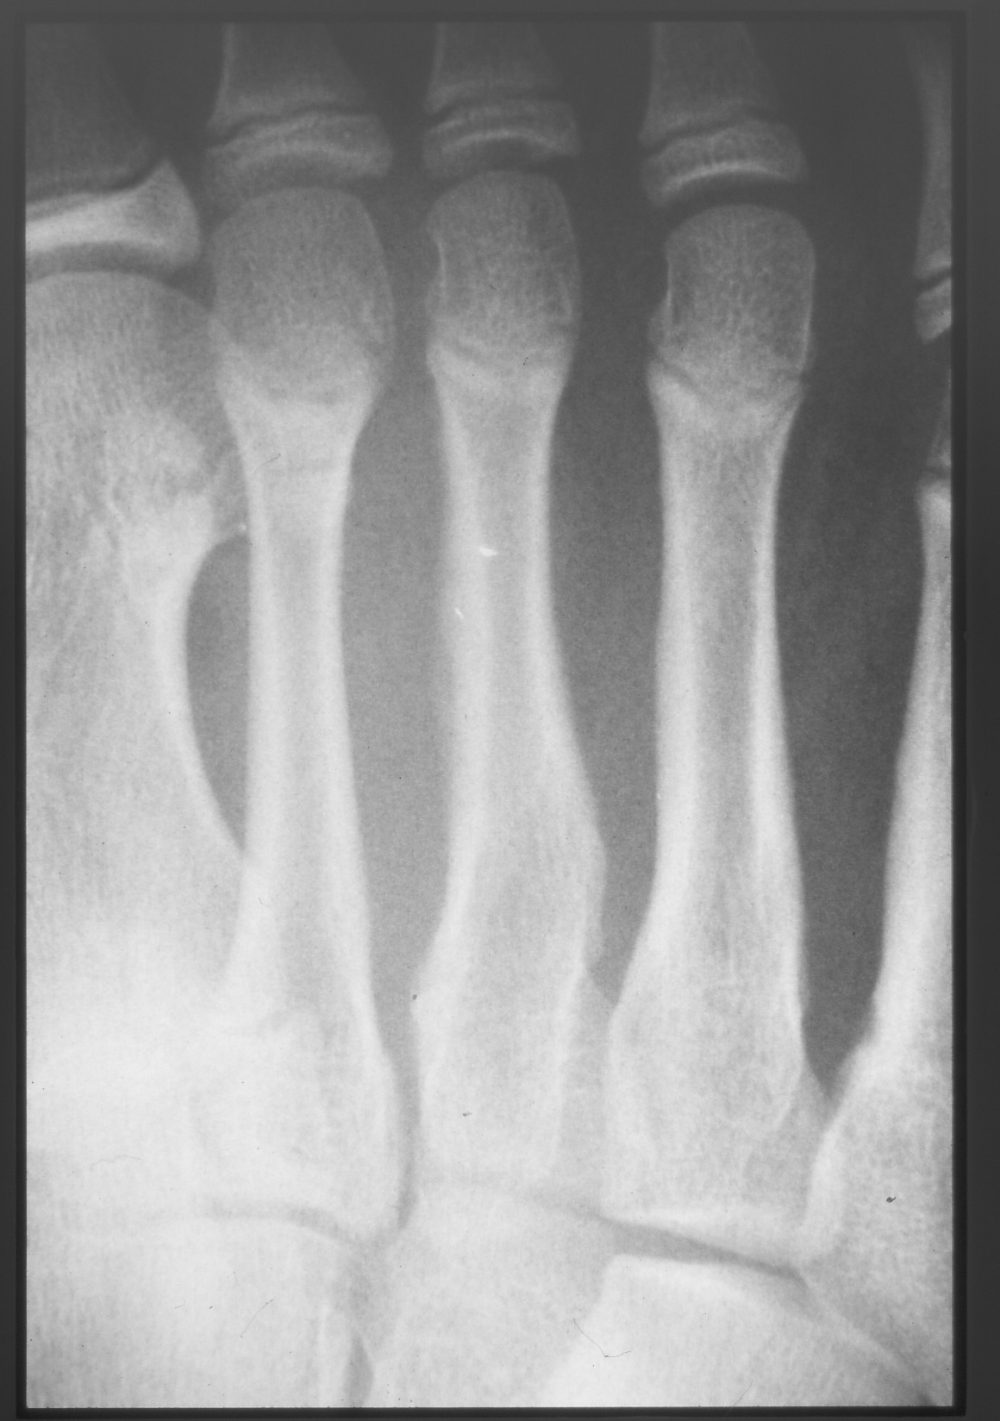

A 15-year-old male soccer player played three hours a day on weekdays, half a day on Saturdays, and a game on Sundays, almost every day of the week. Pain appeared in the dorsum of the right foot, but the patient still continued to practice, and the pain worsened 3 weeks later, so he came to the hospital. The first visit showed tenderness and movement pain in the mid-dorsum of the foot, which did interfere with play, but did not cause problems in daily life. An X-ray showed a callus in the shaft of the third metatarsal bone (Fig. 3).

Figure 3: First visit

There is no obvious fracture line at the initial diagnosis, and there is slight callus formation in the third metatarsal shaft.